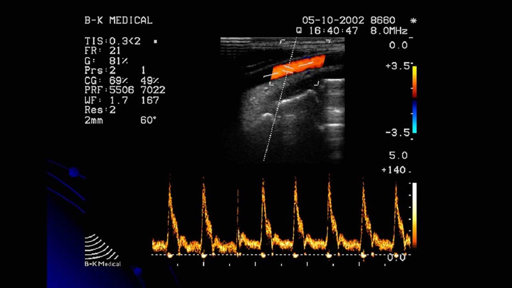

Siêu âm mạch chi dưới là gì, khi nào nên thực hiện?

Sự ra đời của phương pháp siêu âm mạch máu có ý nghĩa quan trọng, giúp hỗ trợ chẩn đoán các bệnh lý liên quan đến mạch máu. Siêu âm mạch chi dưới chính là chủ đề mà MEDLATEC muốn chia sẻ trong bài viết hôm nay. Hãy cùng chúng tôi tìm hiểu và cập nhật thêm những kiến thức hữu ích về kỹ thuật này nhé.

Những điều mẹ bầu cần biết khi siêu âm doppler thai

Khi muốn biết tình trạng sức khỏe, thể trạng của bé thì các mẹ sẽ được khuyến cáo đi siêu âm để đo nhịp tim, mạch máu rốn, mạch máu não,... của thai nhi. Tuy nhiên không phải phương pháp siêu âm nào cũng tối ưu, an toàn. Trong đó, siêu âm doppler thai là phương pháp đư...